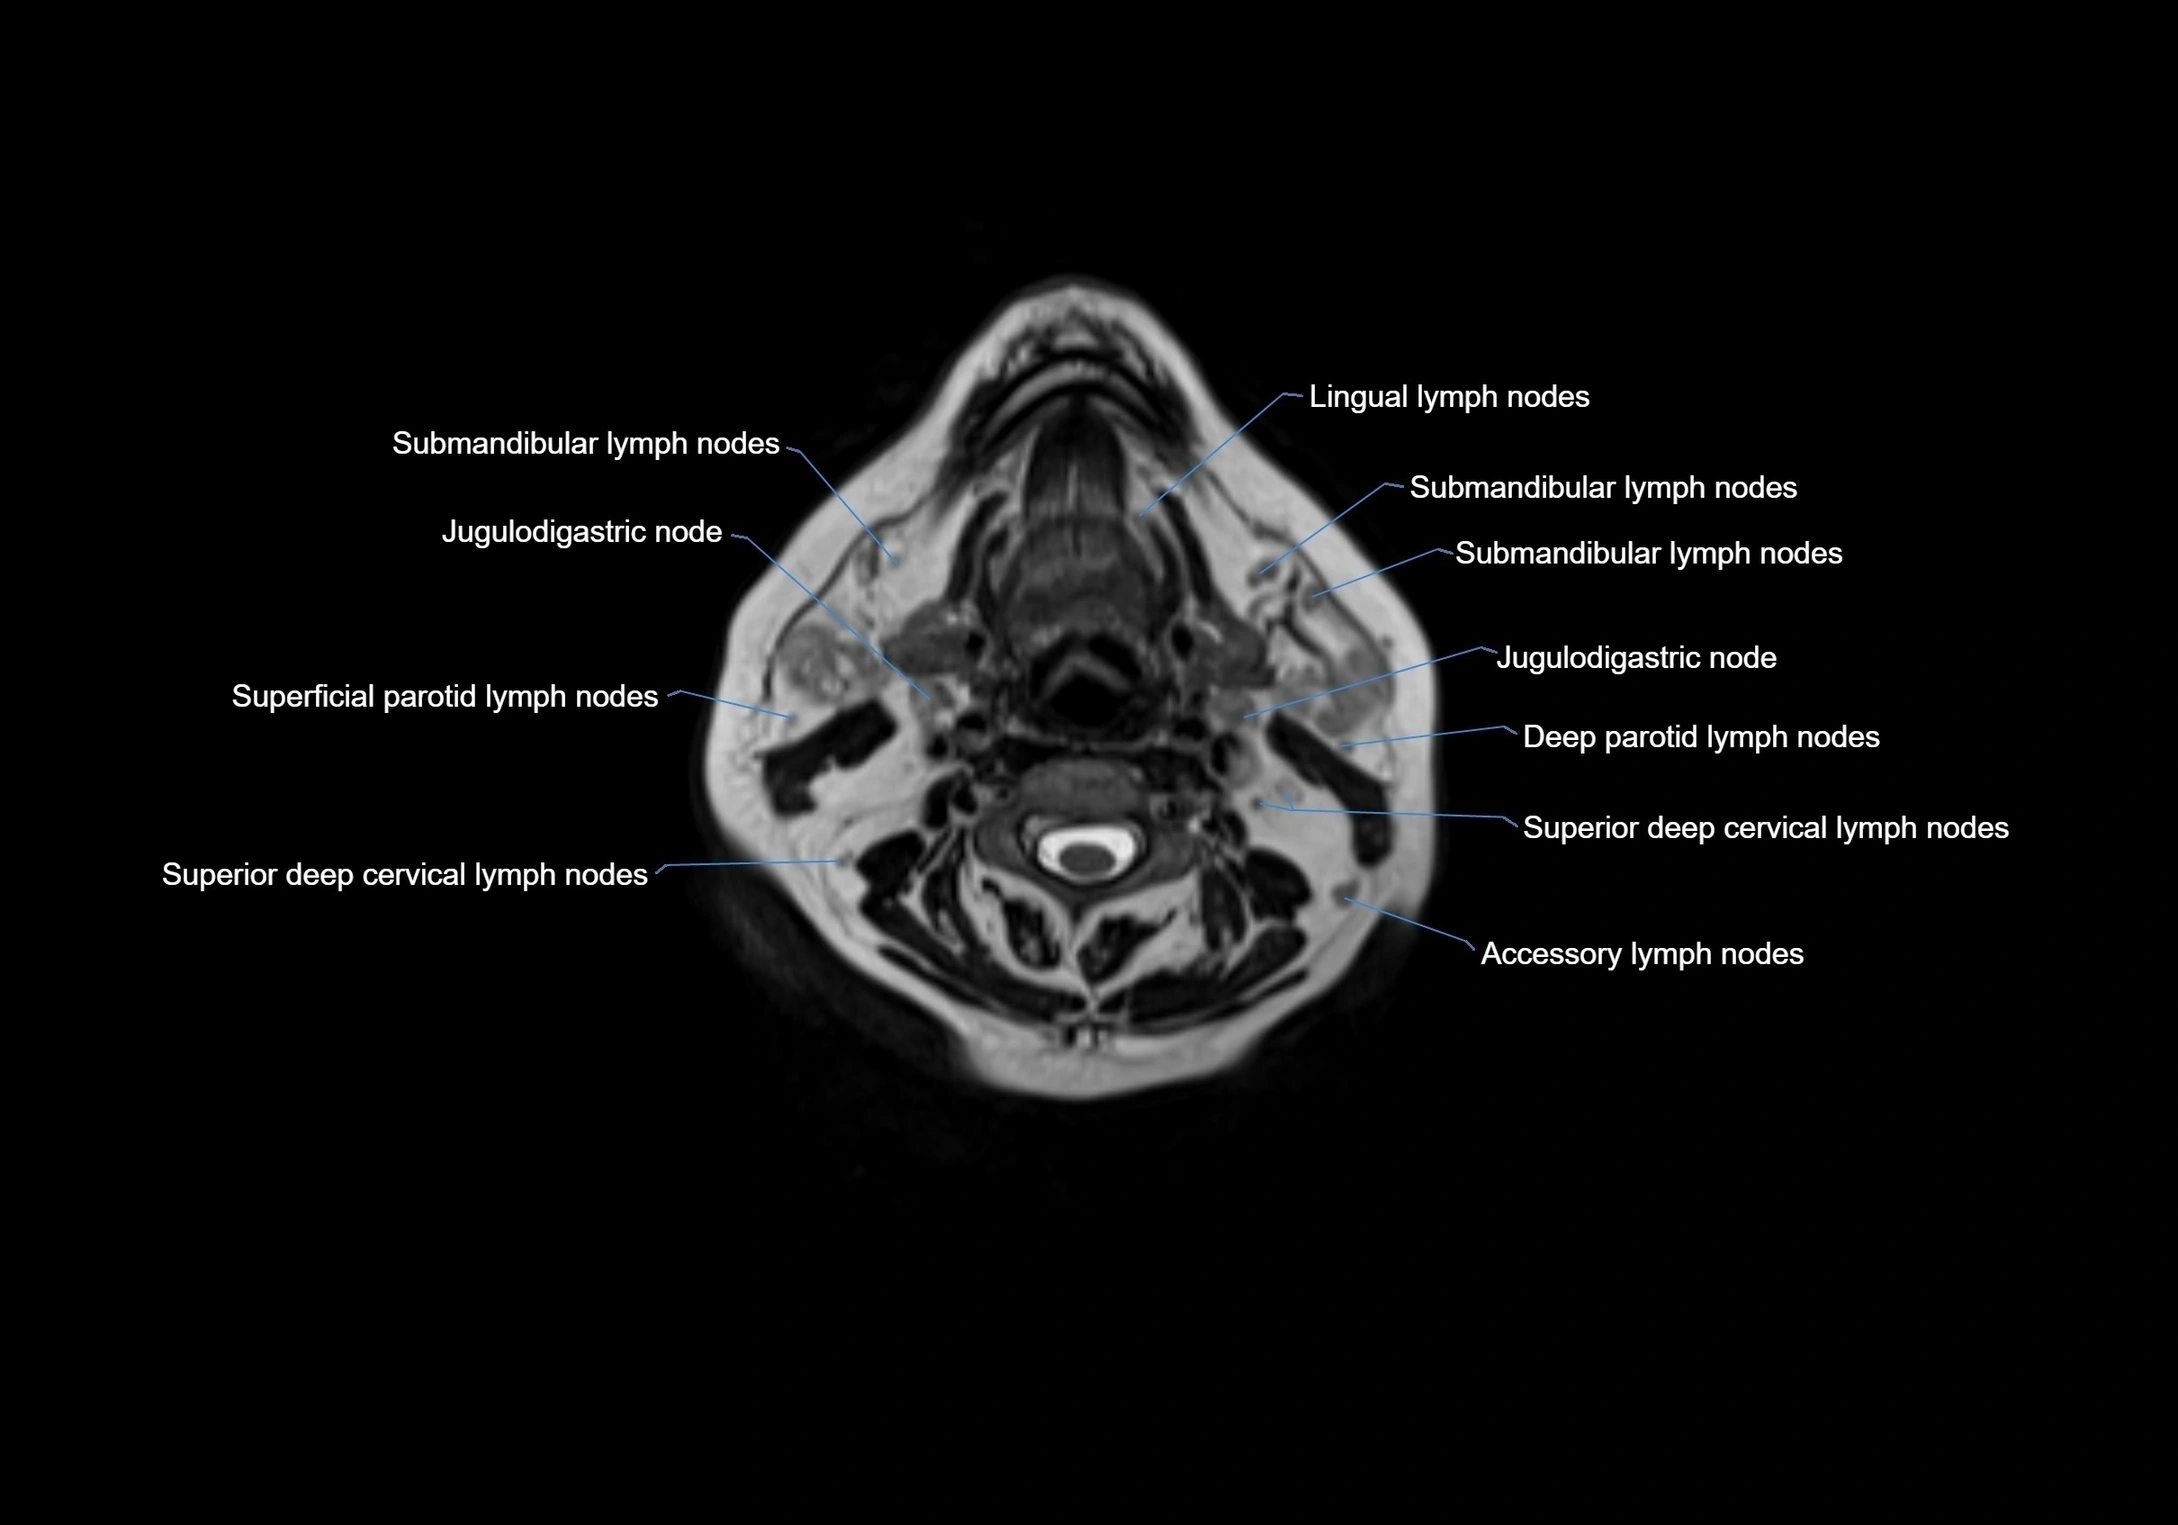

MRI images

image